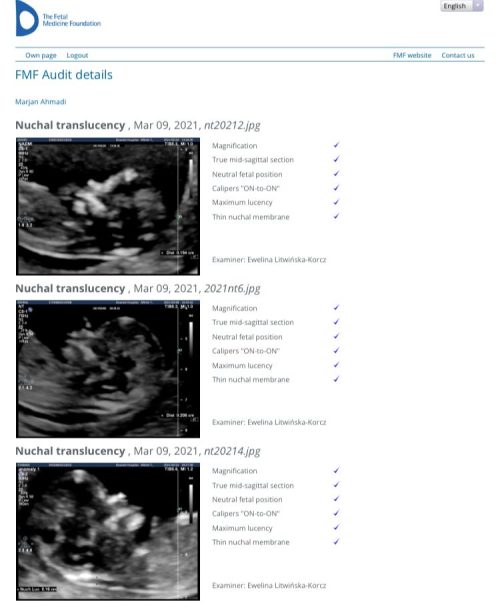

دارای گواهینامه غربالگری و سونوگرافی پیشرفته جنین

از انجمن FMF انگلستان

گواهی نامه ها (از انجمن FMF انگلستان)